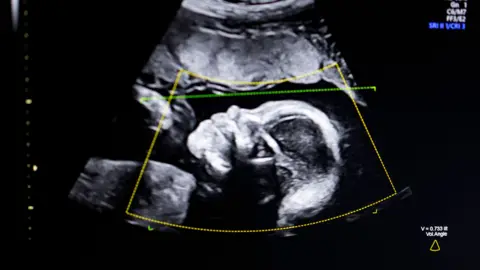

Getty Images An image of a baby's head shown on screen on an ultrasound scan. It is a grainy black-and-white image of the side of the head. You can clearly see the nose and eyes. Overlaid on the top of the image are data from the imaging machine including a yellow box and a green dotted line.Getty Images